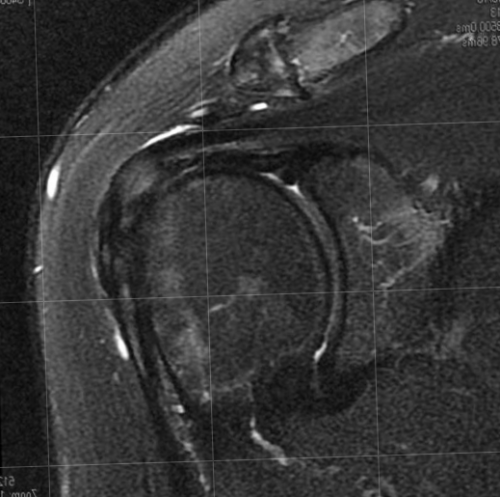

ротаторной манжеты нижней головой (например броски, игра в теннис, волейбол, тяжелая атлетика, плавание и др.).жизни.Патологию ротаторной манжеты